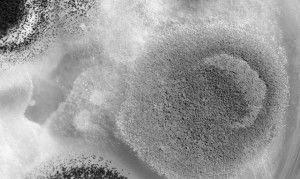

Грибковий або кандидозний стоматит у дитини - це часте явище. Зовні його неможливо переплутати з іншим захворюванням, так як для молочниці в роті характерний білуватий наліт, які легко зчищається.

- білястий густий наліт на зворотному боці щік, на язику і на небі,

Наліт легко можна зняти, однак після цього можливе легке кровотеча і хворобливість. Протягом декількох годин на очищеному місці знову утворюється наліт.